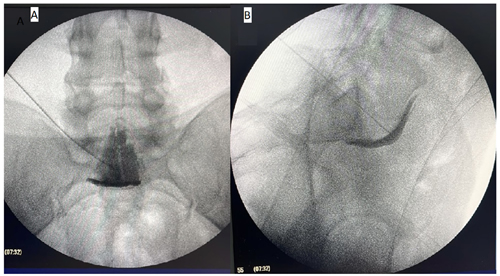

Figura 1

Figura 2